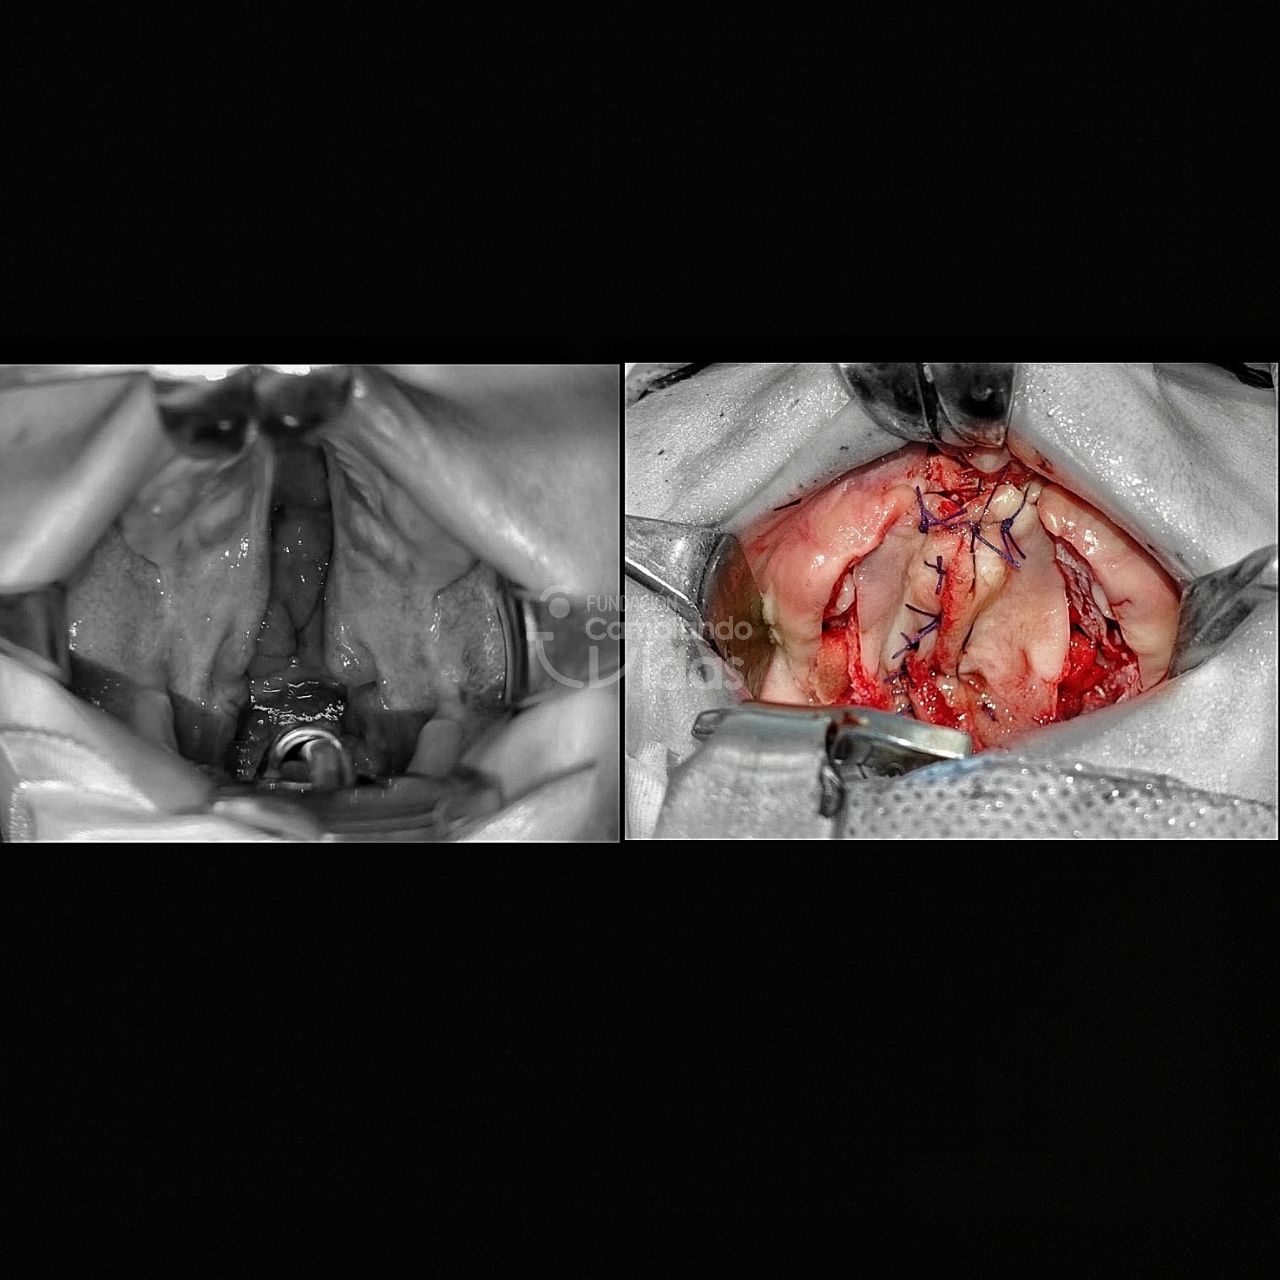

Julia Baralt

Diagnóstico: Lactante de 15 meses de edad con Hipoxia Cerebral y Hendidura Palatina

Intervención Quirurgica: Palatoplastia Primaria

Junior Hernández

Diagnóstico: Escolar con Hendidura Labial Unilateral y Palatina Completa